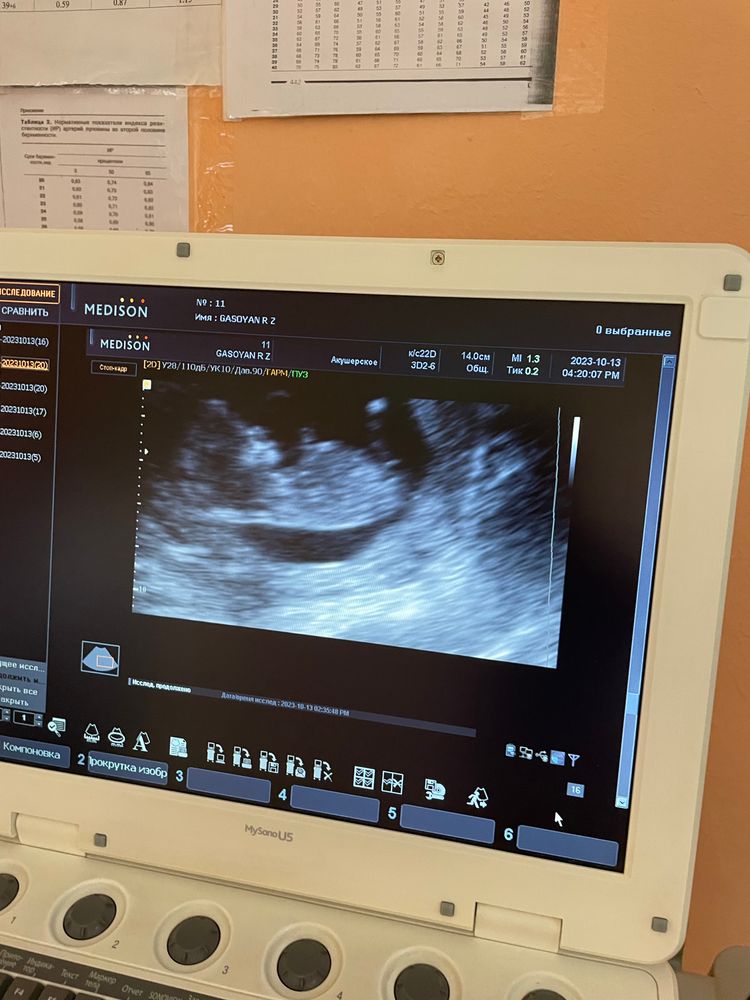

УЗИ беременных в Красноярске

Добрый день, девушки, не хочется ждать 2ой скрининг в 21 неделю, хочется узнать пол деток пораньше, в недель 17. Подскажите, кому приходилось, в каких платных клиниках в Красноярске хорошо делают?

Сейчас нахожусь на 18 неделе беременности, на 16 неделе сказали что девочка 70%,органы женские врач говорила, недавно ходила на узи пока подтверждают. Может ли быть ошибка в поле?

С первым 2 раза ошиблись, но прятался на узи. Это конечно было 5 лет назад, аппараты были не то.

Была на УЗИ в 20 недель беременности и сказали, что девочка и там на экране было видно, что между ножек ну вообще нет никакого намёка на мальчика. Сходила на УЗИ вчера, на 30 неделе и говорят уже мальчик... Было ли у кого-то так и какая вероятность, что ошиблись

Ошибка пола на узи 18 недель

Привет,девочки) Вчера ходила на узи 18недель, попросила посмотреть пол ребенка, сначала врач сказал,что очень рано смотреть пол(живем в германии), а потом сказал,что девочка. А на 12 неделе говорили мальчик,и по расчетам тоже говорили мальчик. Теперь сижу и покоя нет,могли ли ошибиться с полом. У кого нибудь такое было? Ошибались на узи с полом